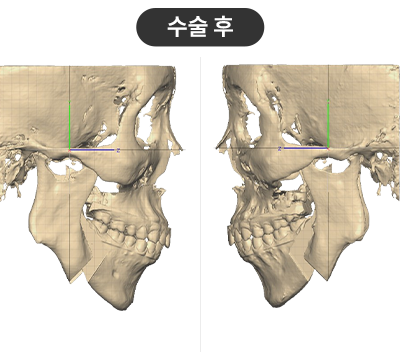

무턱이 심한 환자로, 턱을 앞으로 빼서

정상 범위 내로 개선을 희망

STEP 02

무턱 교정을 위해 하악을 앞으로 이동시켜 적정한 교합을 맞춤

수술결과

무턱 개선 : 턱 끝 기준 14mm 전진